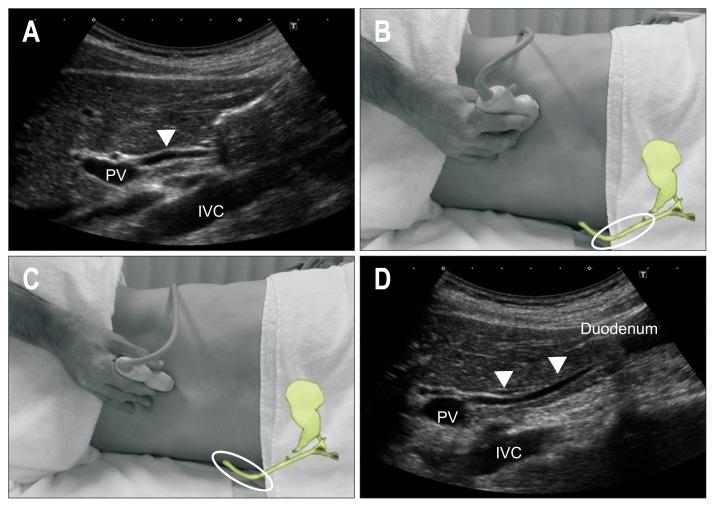

As ultrasound (US) is simple and less invasive than other imaging modalities, this technique is widely used for mass screening. However, visualizing the entire pancreas due to complicated anatomy, obesity and overlying gas can be difficult. US plays a key role in the diagnosis of pancreatic carcinoma (PC), of which tumors smaller than 10 mm (TS1a) and pancreatic carcinoma are expected to have good prognosis. To detect these forms of PC, main pancreatic duct (MPD) dilatation (3 mm or more) and pancreatic cysts (5 mm or larger) are US findings of high-risk individuals (HRIs), and these subjects should be observed periodically. Scanning maneuvers are also important for both screening for PC and follow-up of HRIs. As lesions in the groove area and ventral pancreas do not affect the MPD or extrahepatic bile duct, we should pay attention to these areas. Visualization of the tail is also challenging due to gas and stool in the alimentary tract. As the position of the pancreas changes depending on the body posture, and several different body positions should be employed, such as the right lateral decubitus, sitting, and upright positions, rather than only applying strong compression with the transducer. In cases with poor visualization, the liquid-filled stomach method is highly recommended.

由于超声(US)比其他成像方式简单且侵入性更小,因此该技术被广泛用于大规模筛查。然而,由于胰腺的复杂解剖结构、肥胖和上方气体的影响,很难对整个胰腺进行可视化。US 在胰腺癌(PC)的诊断中起着关键作用,其中直径小于 10mm(TS1a)和胰腺神经内分泌肿瘤的肿瘤预计具有良好的预后。为了检测这些形式的 PC,主胰管(MPD)扩张(3mm 或更大)和胰腺囊肿(5mm 或更大)是高危人群(HRIs)的 US 发现,这些患者应定期观察。扫描手法对于 PC 的筛查和 HRIs 的随访也很重要。由于沟区和胰头区域的病变不会影响胰管或肝外胆管,因此我们应该注意这些区域。由于消化道中的气体和粪便,尾部的可视化也具有挑战性。由于胰腺的位置随体位变化而变化,因此应采用几种不同的体位,如右侧卧位、坐位和立位,而不是仅用探头进行强力压迫。在可视化效果不佳的情况下,强烈推荐使用充满液体的胃法。